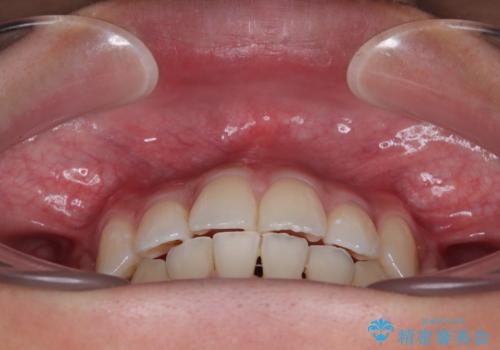

患者様の望んでいた通りの歯列や口元に仕上げることができました。

- 八重歯と口元の閉じにくさを気にして来院された患者様です。

非抜歯矯正で歯列を整えると、治療後に口元が今よりも突出する可能性が高かったため、上下左右の第一小臼歯4本を抜歯し、ワイヤー装置にて矯正治療を行うこととしました。